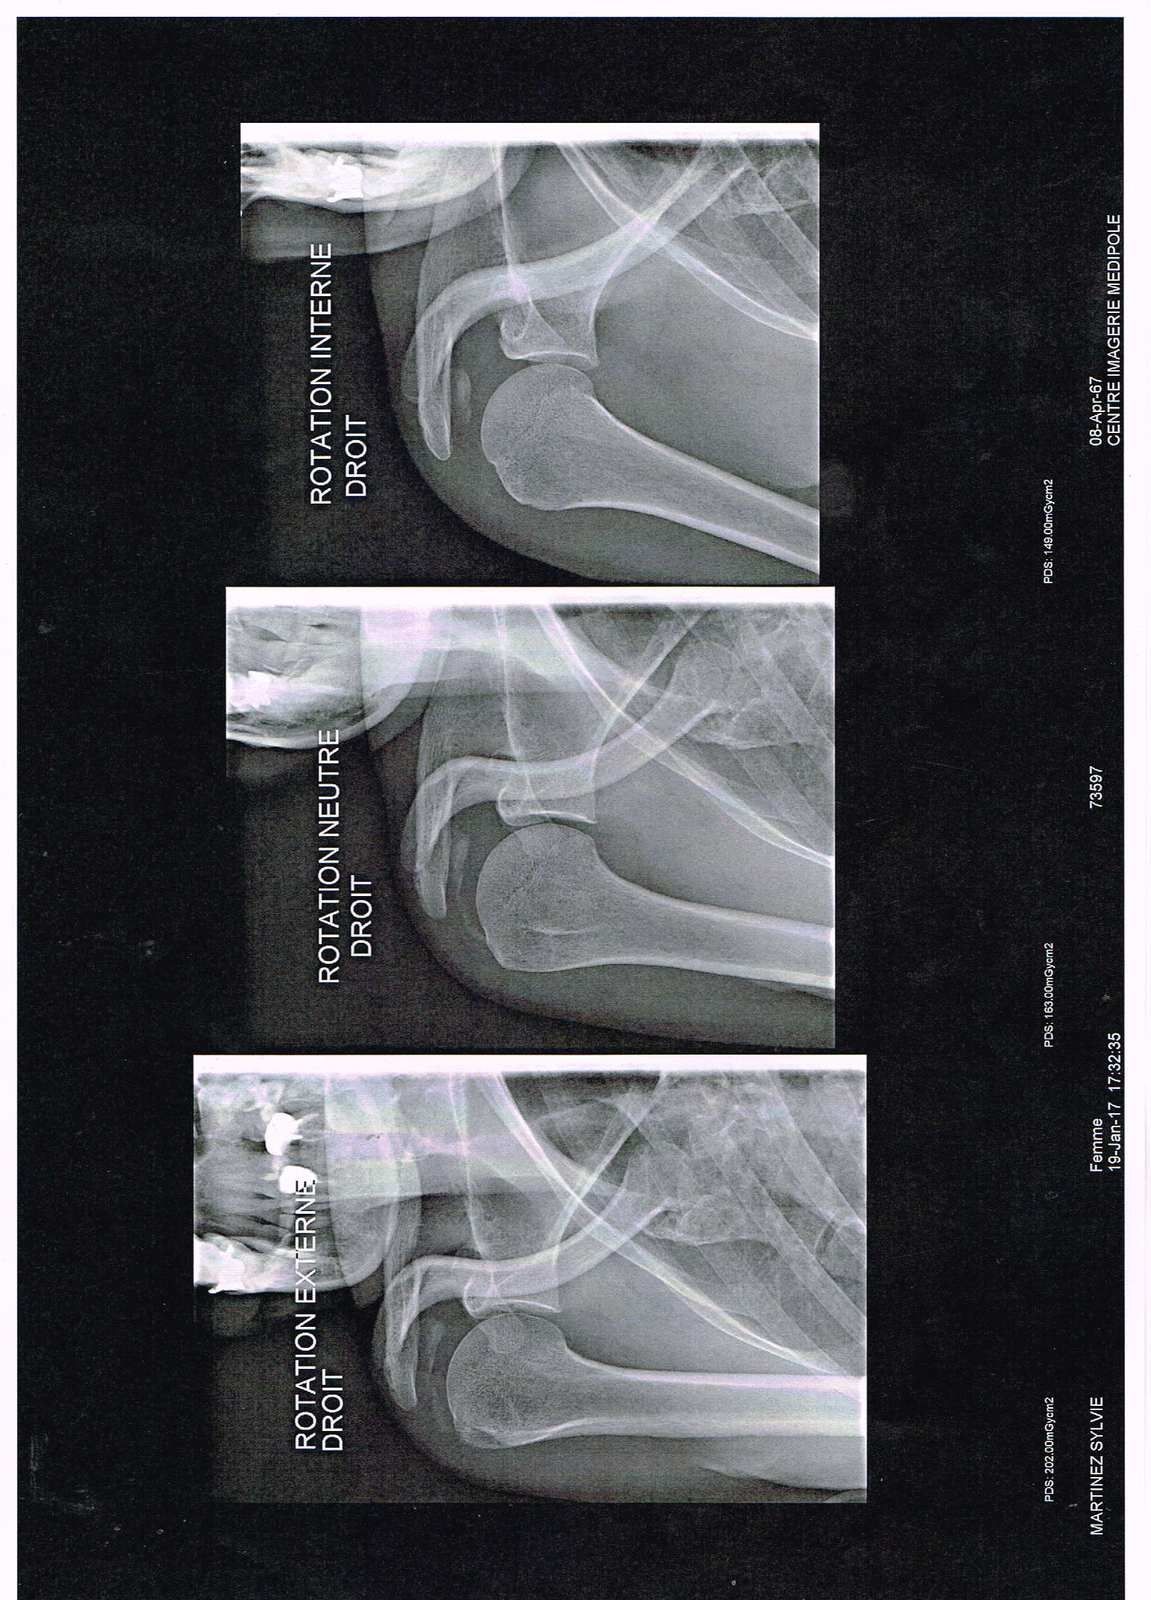

Il comportait 3 clichés de faces en rotation neutre, en rotation interne et en rotation externe, un profil de BERNAGEAU, à la recherche · Des fractures du rebord antéroinférieur de la glène · D’encoche humérale · D’érosion de la glène · D’ostéophyte huméral, signant le début d’une arthrose glénohumérale. Radiographie de face en rotation neutre et Faux profil de Lamy Medical illustration of the shoulder's muscles superficial layer with deltoid, trapezius, pectoralis major and minor, latissiums dorsi. Après une réparation d’une lésion tendineuse de stade 1 ou 2 immobilisation par attelle en rotation neutre pendant 4 semaines La mobilisation en « pendulaire » sera débutée dès que possible par le patient luimême, sans créer de douleurs, à un rythme de croisière de 5 minutes 5 fois par jour.

Le bilan d’imagerie d’une omarthrose doit permettre d’évaluer l’état de destruction de l’os et du cartilage et l’aspect des muscles et des tendons Le bilan radiographique standard sera assez complet avec 1/ 3 radiographies de face à 3 niveaux de rotation du bras (neutre, interne et externe). Il est possible d'avoir recours à une radiographie classique avec des clichés de face en position neutre et en rotation à la recherche avant tout de calcifications Les autres examens seront indiqués en fonction des premières orientations fournies par les caractéristiques de la douleur. Il comportait 3 clichés de faces en rotation neutre, en rotation interne et en rotation externe, un profil de BERNAGEAU, à la recherche · Des fractures du rebord antéroinférieur de la glène · D’encoche humérale · D’érosion de la glène · D’ostéophyte huméral, signant le début d’une arthrose glénohumérale.